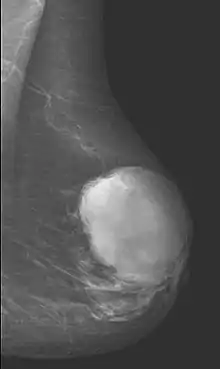

Diagnostic Techniques

Radiographical imaging is the first-line test for identifying a phyllodes tumor.[11] Despite their propensity to grow rapidly and deform the overlying breast tissue, approximately 20% of phyllodes tumors can present as a nonpalpable mass on screening mammography.[12] Other imaging tools used to assess the size and spread of a phyllodes tumor include ultrasound and magnetic resonance imaging (MRI).[11] None of these imaging tools are definitive tests for differentiating a phyllodes tumor from a benign fibroadenoma.[13] Phyllodes tumors can only be diagnosed histologically, as they tend to have many overlapping features with other breast masses on physical examination and radiological imaging.[11]